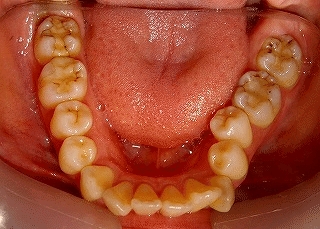

上顎前突(非抜歯)

術後